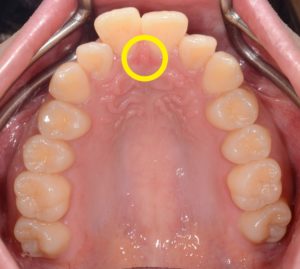

理想の舌の位置(=「スポット」)は、上あごの前歯の少し後ろの天井部分。

舌先をここに置き、前歯を触らずに飲み込むのが正しい位置です。

Week1:舌の位置を知る(スポットを覚える)

舌先を上あごのスポットに軽く当てて3分キープ × 1日3回